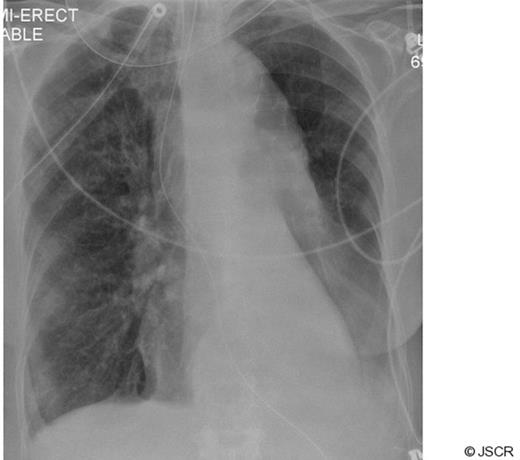

CT scanning revealed a large descending thoracic aortic aneurysm measuring 8 cm in maximum diameter (Fig 2). The left main bronchus was compressed between the aneurysm and the aortic trunk (Fig 3). The patient was regarded as unfit for an open replacement of the aneurysm. The neck of the aneurysm was markedly conical immediately distal to the left subclavian artery, so proximal stent graft placement would have necessitated left common carotid artery and left subclavian artery bypass grafting to provide a parallel proximal landing zone. The distal neck was also markedly conical with a diameter of 42 mm at the coeliac axis, with extensive mural thrombus. These features rendered a successful endovascular repair unlikely, and therefore endovascular interventional was discounted.

CT chest showing complete compression of left main bronchus by large aortic aneurysm